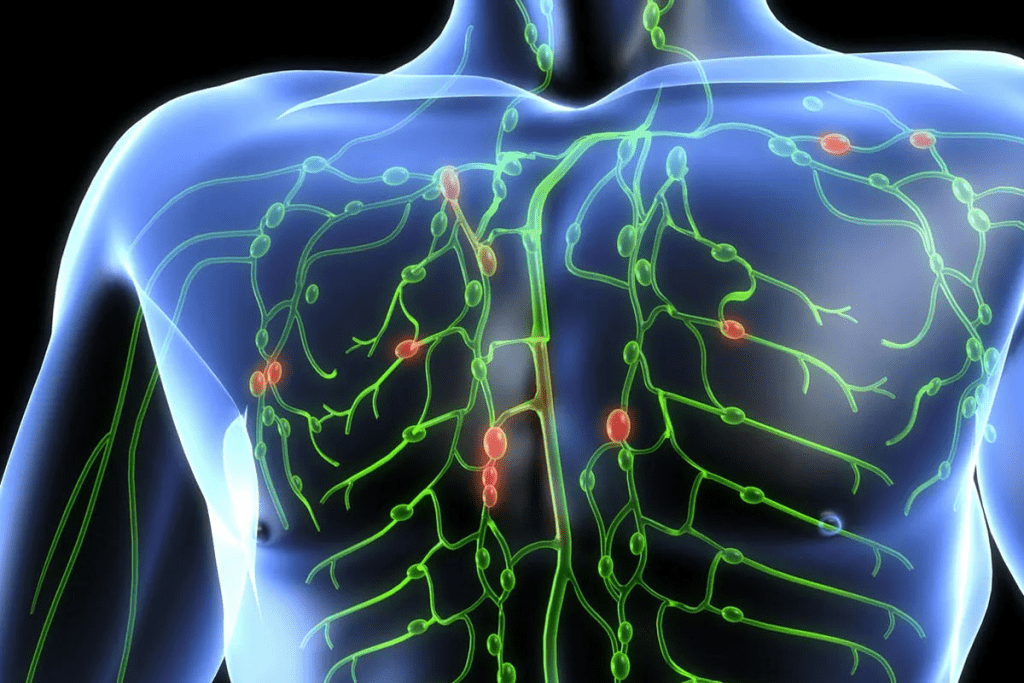

Why doctor recommend PET scan

Why Doctor Recommend PET Scan: Medical Reasons and Diagnostic Benefits 5

PET scans are a big step forward in medical imaging. They let doctors see how organs work in real time. This is key for spotting and treating diseases, like cancers.

How PET Imaging Works

PET imaging uses a special tracer that’s injected into the body. This tracer goes to areas with lots of activity, like cancer cells. The PET scan picks up this tracer, showing how different body parts work.

The ability to see how cells work in real-time makes PET scans great for finding and tracking lung cancer.

Difference Between PET and Other Imaging Techniques

PET scans are different from CT or MRI scans. While CT and MRI show what organs look like, PET scans show how they function. This is important because PET scans can spot changes at the cellular level before other scans can.

• Functional vs. Anatomical Imaging: PET scans show how an organ works, while CT and MRI show its structure.

• Early Detection: PET scans can find diseases like cancer sooner than other scans by showing abnormal activity.

PET scans are a powerful tool in today’s medicine.